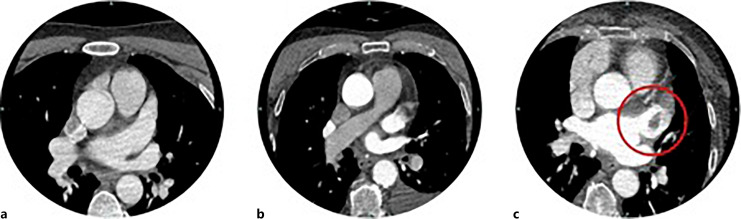

Methods: We extended the CTA scan range of acute stroke patients 4 cm below the carina to include the left atrium and appendage. During the review, we evaluated LAA thrombi based on contrast relations. We then used gradient boosting to identify the most important predictors of LAA thrombi from a variety of different clinical parameters.

Results: We examined 240 acute stroke patients' extended CTA scans. We detected LAA thrombi in eleven cases (4.58%), eight of them had atrial fibrillation. 23.75% of all patients (57 cases) had recently discovered or previously known atrial fibrillation. Windsack morphology was the most commonly associated morphology with filling defects on CTA. According to the gradient-boosting analysis, LAA morphology showed the most predictive value for thrombi.

Conclusion: Our extended CTA scans reliably detected LAA thrombi even in cases where TTE did not and showed that 2 patients' LAA thrombus would have been untreated based on electrocardiogram monitoring and TTE. We also showed that the benefits of CTA outweigh the disadvantages arising from the slight amount of excess radiation.

Abstract Image